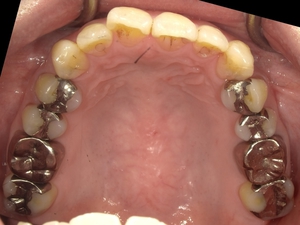

Before After

●ご相談内容:前歯が曲がっている●矯正の種類:マウスピース型「矯正インビザラインGO」●治療期間:18週●治療費用:66万円(税込)